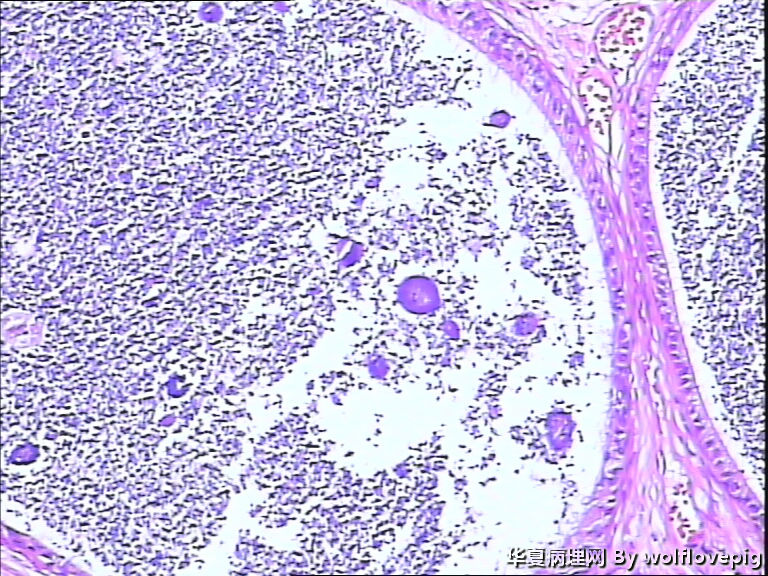

62y,双侧附睾。

送检附睾管囊性扩张,管腔结构较完整,多数管腔内见精子积聚,少数管腔内有出血。

取材切片附睾管扩张,精子淤积,部分区域出血

未见肉芽肿结构,也未见其它异常。

有出血,腔内大量精子,未见特异病变